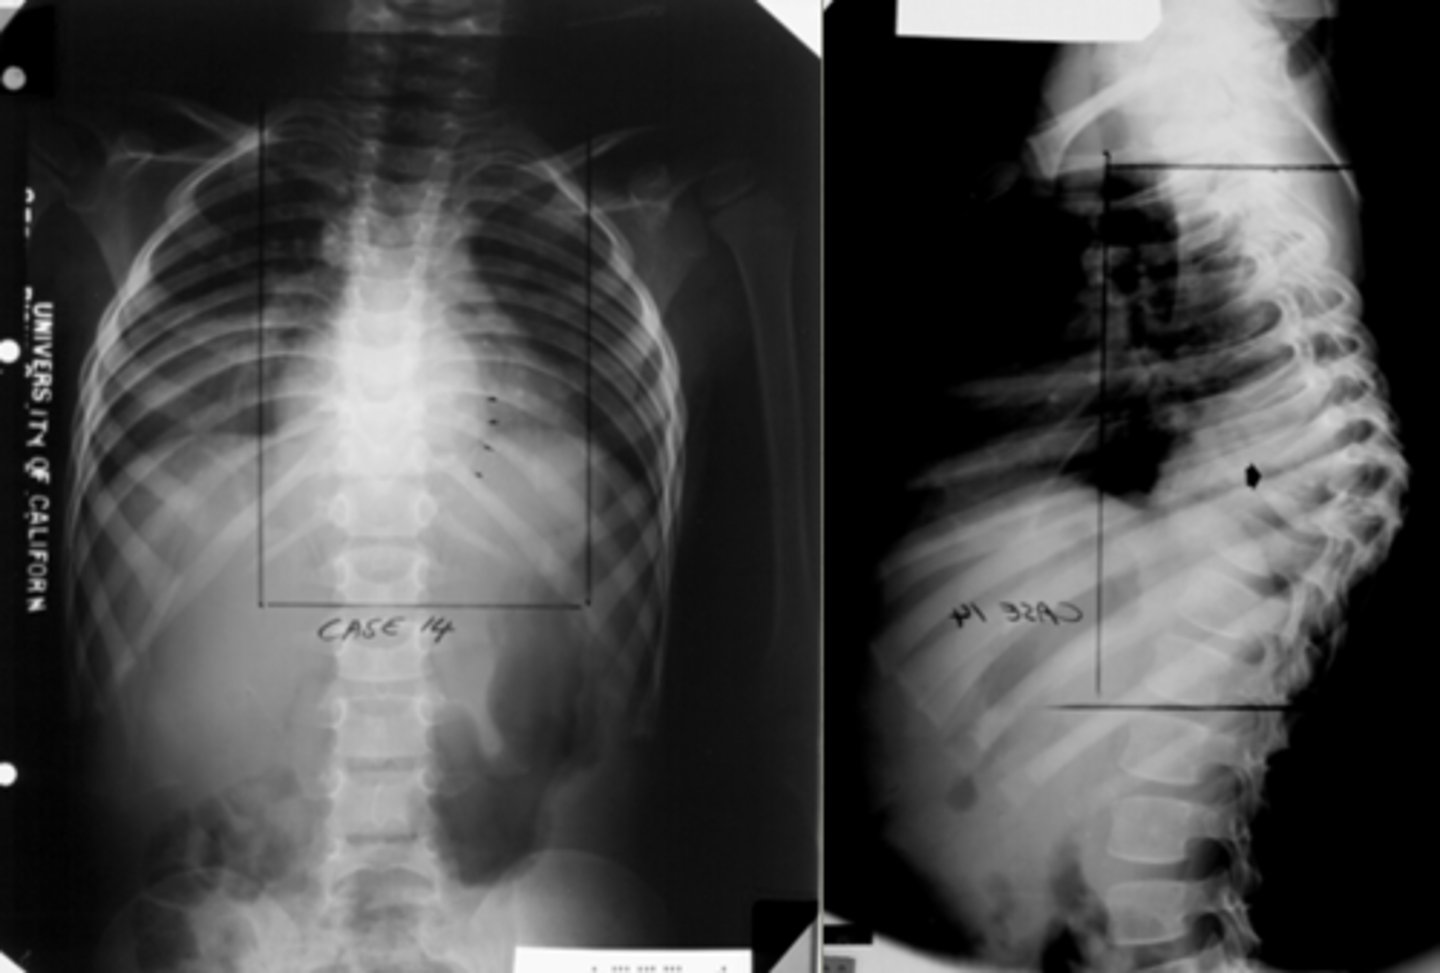

Over-curvature of the thoracic vertebrae, commonly seen in the elderly. Looks like humpback

Kyphosis

Spine is curved from side to side

scoliosis

What is gibbus of the spine, which is associated with osteoporosis?

Where the thoracic spine points outward like a camels back